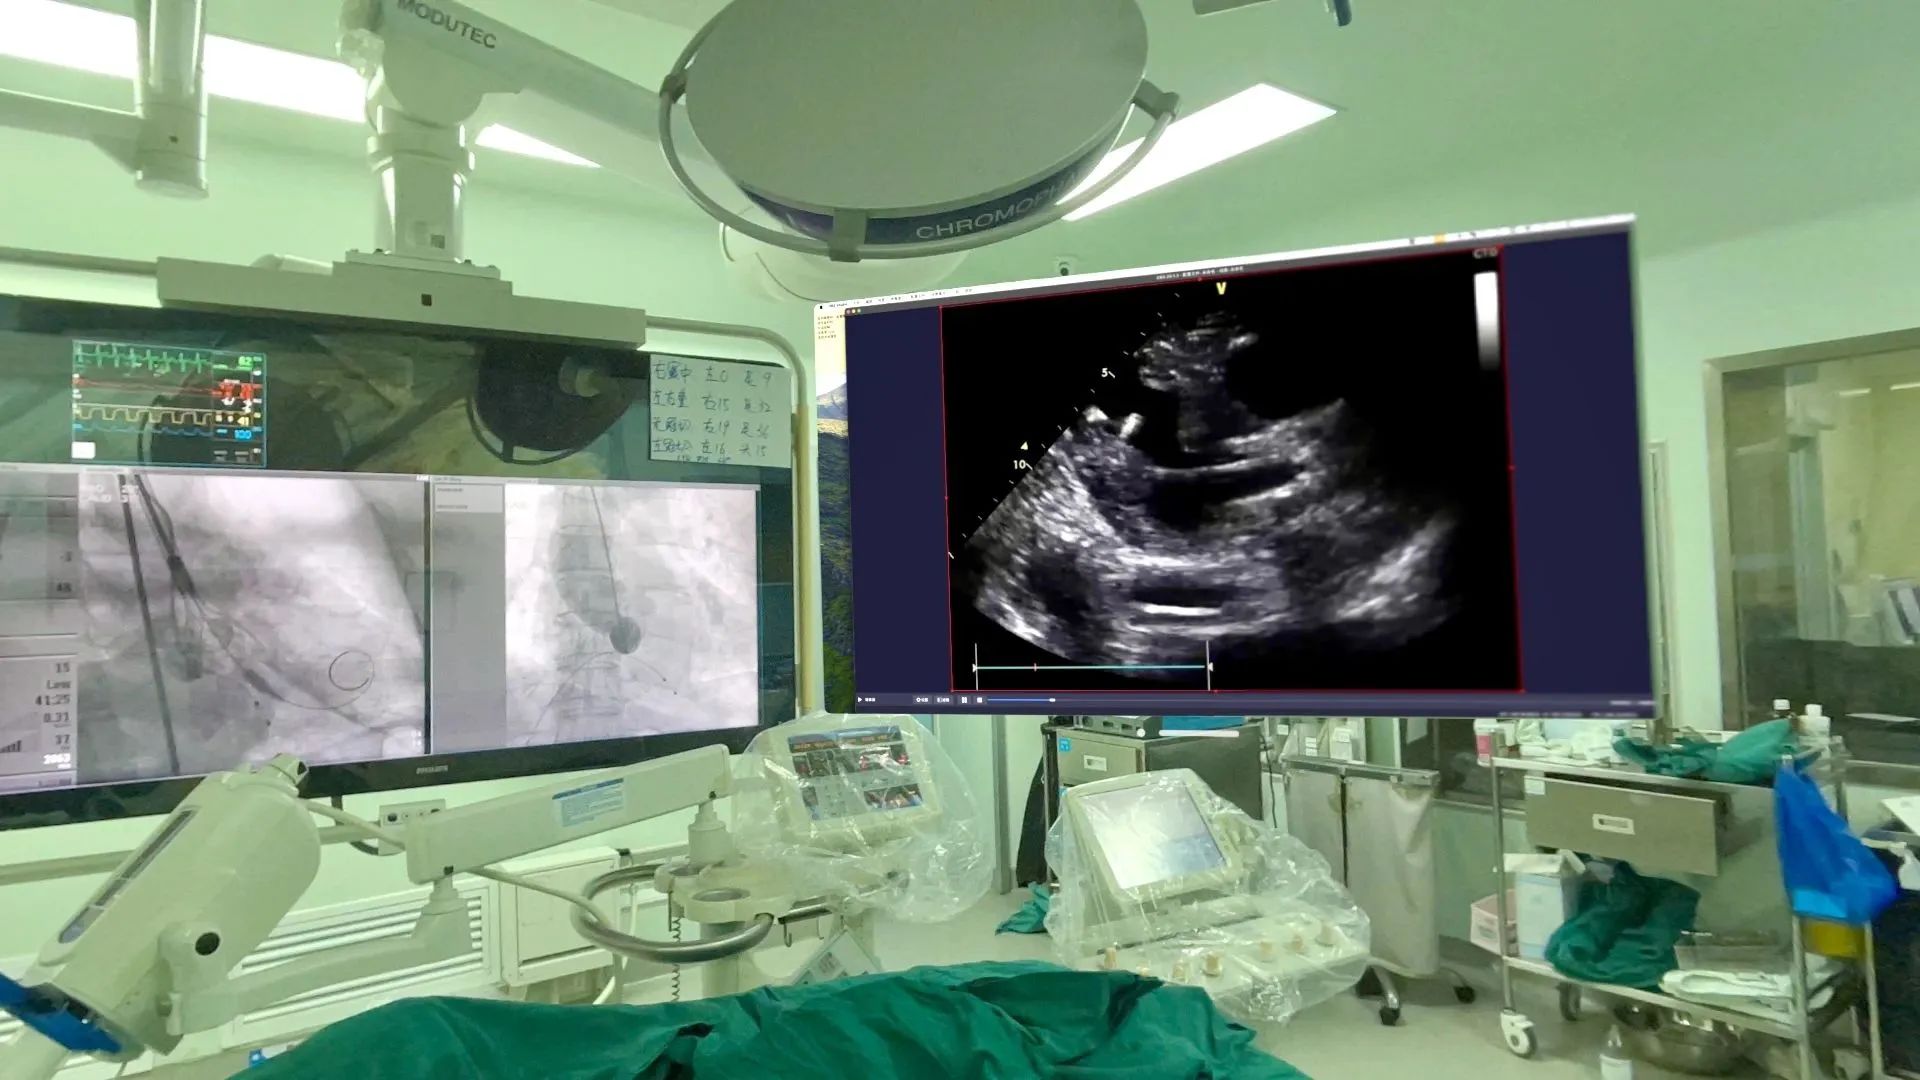

2 其次在术中,团队可以利用该设备先进的增强现实技术,通过高清晰度、大视野的虚拟屏幕向术者呈现极低延时(约50ms)的超声图像,提高了手术操作的精准度和安全性。而以往在术中,术者往往需要停下手术操作、来到超声机屏幕前观察;即使超声机外接屏幕,也存在视野小、挤占手术室空间等问题。因此Apple Vision Pro头显完美解决了术者的用户痛点。且术者可以通过手势操作控制虚拟屏幕的尺寸及位置,不需要触碰机器、不违背无菌操作原则。

TAVR术中场景,左侧为DSA机器悬吊屏幕,右侧为Apple Vision Pro头显的虚拟屏幕